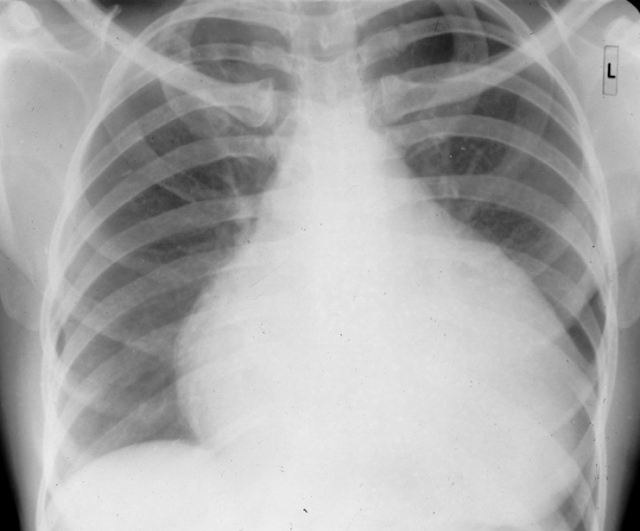

C-Cardiac silhouette(心翦影):看看心臟長啥樣,SIZE如何,假如心臟寬度大於胸腔寬度的一半,可能有心臟肥大(Cardiomegaly)的問題;或者也可能是心包膜積水(pericardial effusion)。

心包膜積水:在CXR上,肥大的方式跟一般的心臟肥大(cardiomegaly)不太一樣,心包膜積水肥的方式比較「圓潤」一點,你會覺得比較像水球,不像是心臟。